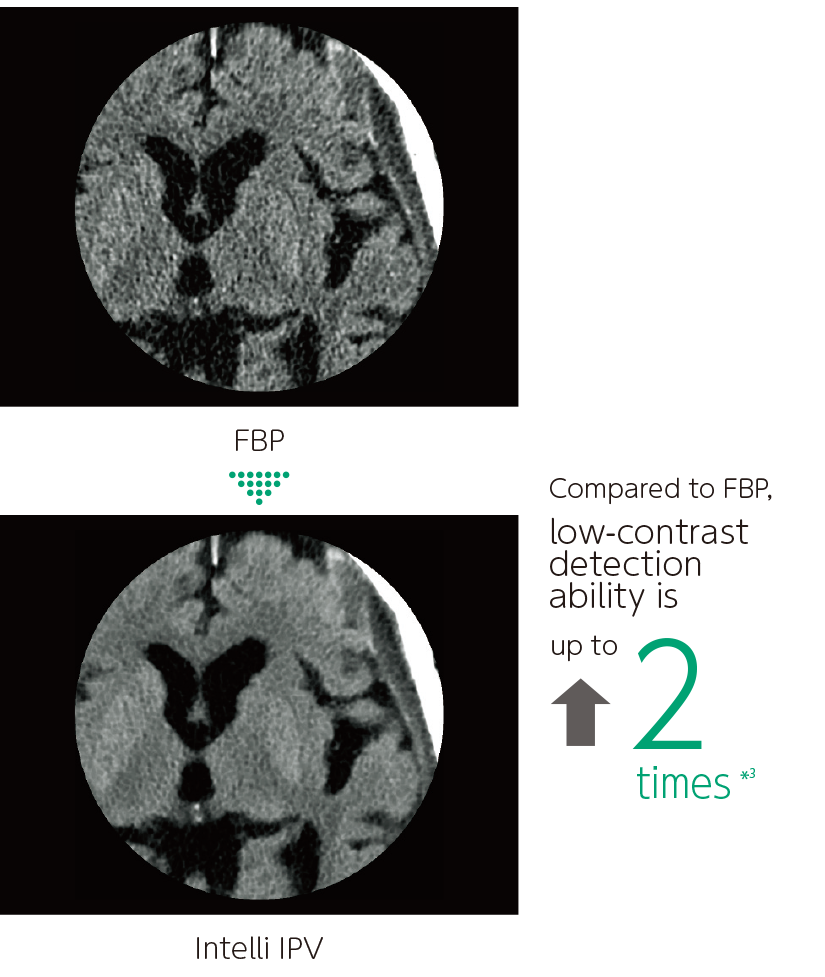

Intelli IPV is an image reconstruction technique developed with AI technology*1. Reconstruction processing has been speeded up by using images obtained through sufficient iterative processing as training data. Based on the Fujifilm's Visual Model, reconstruction processing using RawData brings the NPS (Noise Power Spectrum) closer to FBP (Filtered Back Projection) and keeps the image texture, even at a high noise reduction rate. It reduces image noise by up to 90%*2 and radiation exposure by up to 83%.*3 It also improves low contrast detectability by up to 2 times.*3

Improved low-contrast resolution

- *2 Compared to FBP. It was measured using Intelli IPV intensity level Strong5 and tested to a water phantom. Depending on the clinical task, patient size, anatomic location, and clinical examination, the effect obtained may be smaller.

- *3 Compared to FBP. It was measured at 0.625 mm slice thickness using Intelli IPV intensity level Strong5 and tested to MITA CT IQ phantom CCT189, Phantom Laboratory using the model observer method results. Depending on the clinical task, patient size, anatomic location, and clinical examination, the effect obtained may be smaller.